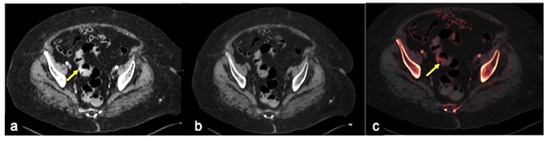

| Rectal Varices and Haemorrhoids (Figure 35) | Pain and/or bleeding. | Dilated veins with possible bleeding visible in the portal phase; rectal varices are located proximal to the linea dentata while haemorrhoids are located in the anus. |